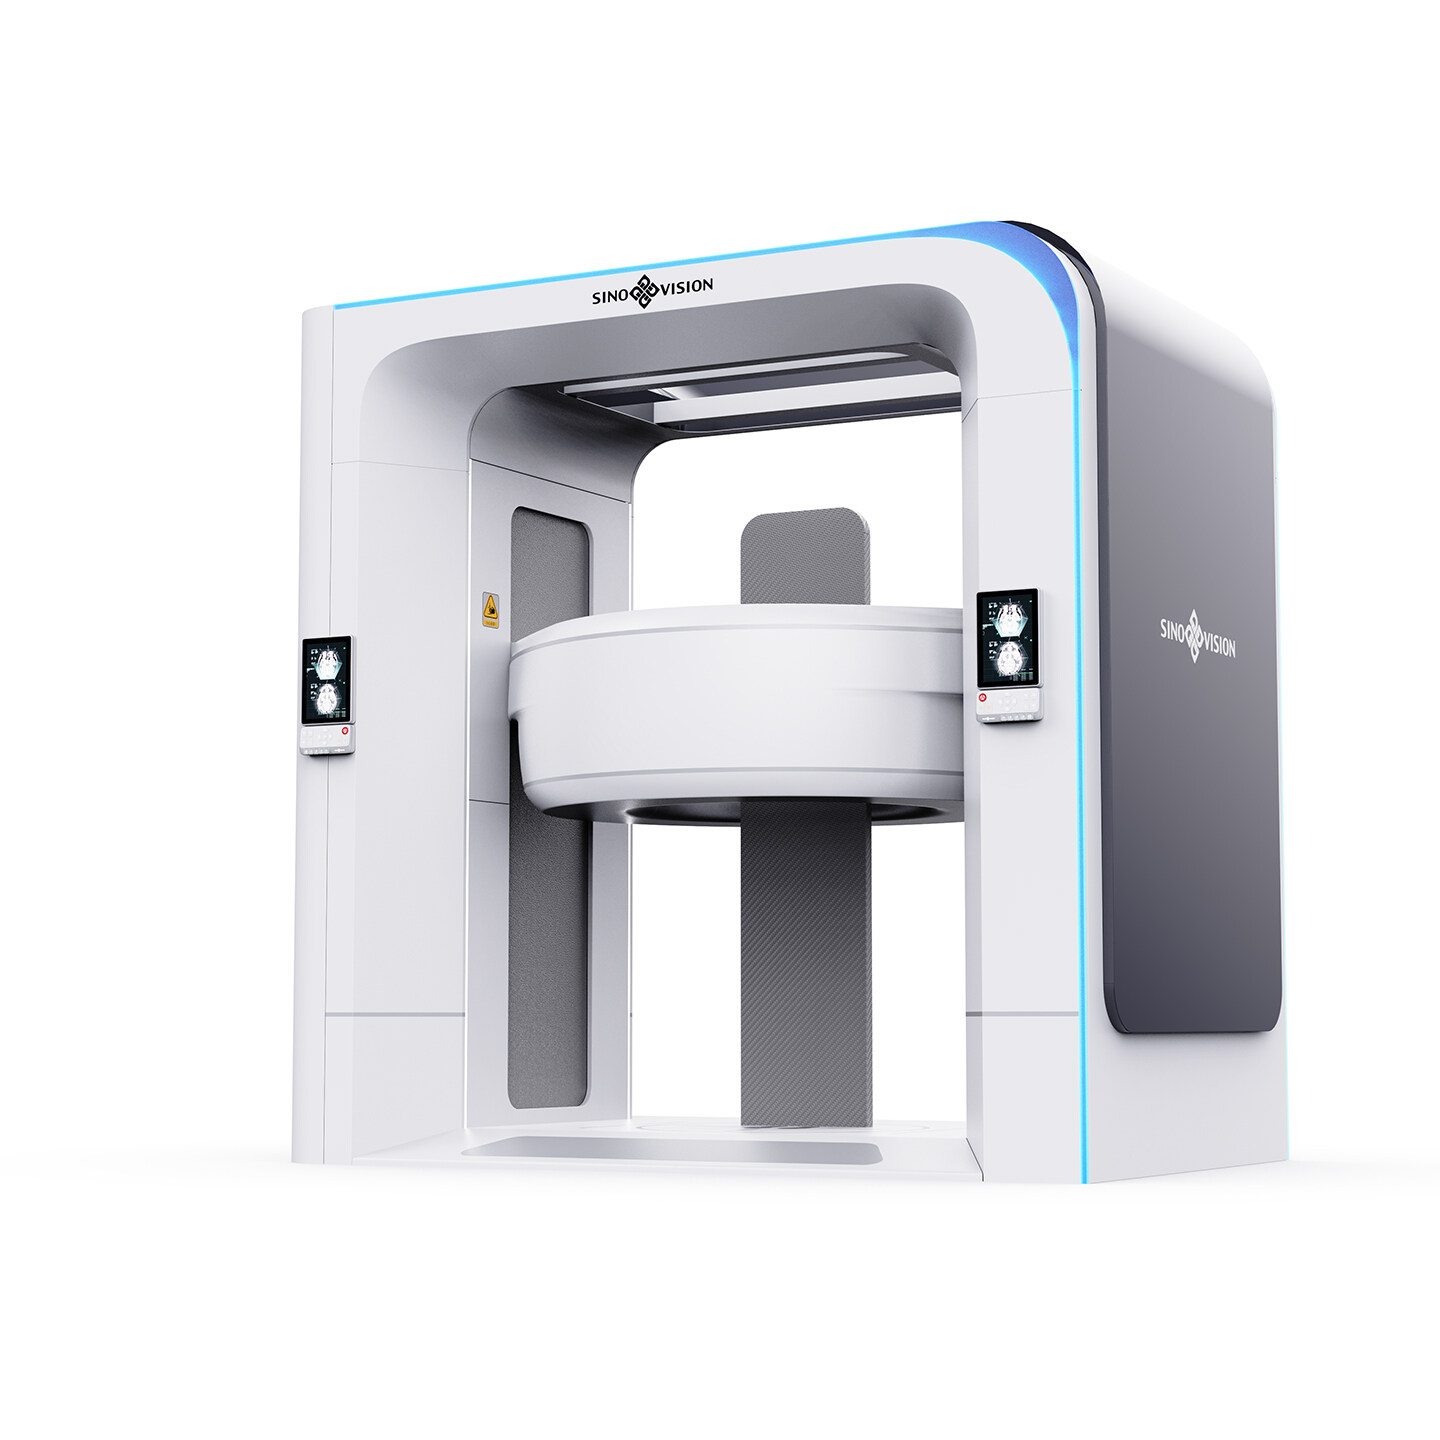

摩登7咨询与设计以市场与技术的迭代更新为导向,业务深入智能制造、消费零售、交通出行、医疗健康、文化创意、公共服务等,多领域横向延伸,全行业覆盖。

摩登7是一家用咨询设计的能力,为垂直行业客户,提供产品创新价值的公司。摩登7坚持以用户体验为核心,致力于为企业提供行业整体创新解决方案。如需创新设计咨询,请联系专家团队。